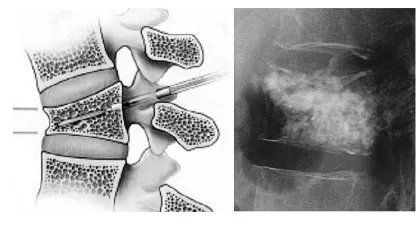

Questo metodo tradizionale e conservativo permette la guarigione della frattura ma non consente la correzione della cifosi vertebrale. Il trattamento chirurgico, invece, pur essendo maggiormente invasivo, permettere di raggiungere risultati più efficaci mediante due possibili interventi: la vertebroplastica e la cifoplastica. Richiedi maggiori informazioni riguardo questi interventi contattando lo studio medico del Dottor Andrea Piazzolla.